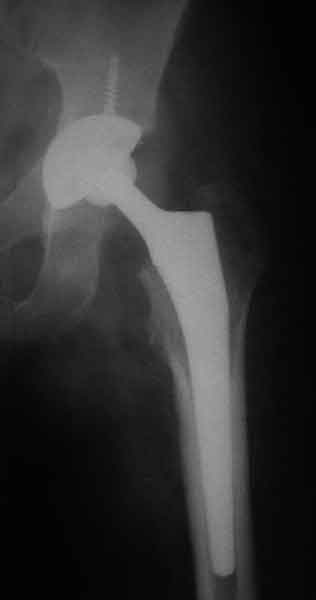

Еще пара фото, ситуация несколько иная, задачи те же, открытое вправление застарелого вывиха в 2002, молодой возраст. Сейчас госпитализирована для эндопротезирования.